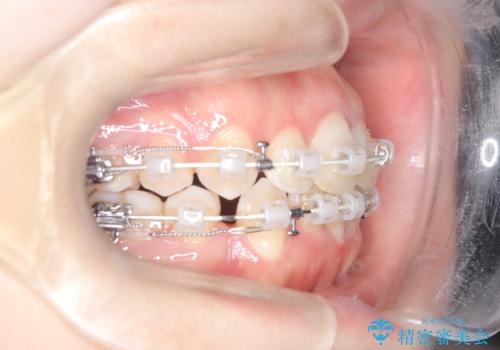

前歯のデコボコと開口を改善し、美しい口元へ

- 前歯のデコボコ(叢生)と、上下の歯が閉じない開口を主訴にご来院されました。精密な検査の結果、歯が並ぶスペースが不足しており、特に奥歯の咬み合わせが安定していないことが開口の原因と判明。患者様と相談し、上下左右の小臼歯を抜歯することでスペースを確保し、審美ワイヤー矯正で全体を整える治療計画を立案しました。これにより、見た目の改善だけでなく、機能的な咬み合わせも獲得することを目指します。

今回の矯正治療では、歯が並ぶスペースを確保するため、上下左右の小臼歯を抜歯しました。装置には目立ちにくい審美ワイヤーを使用し、見た目に配慮しながら治療を進めました。抜歯によってできたスペースを利用して歯を並べ、前歯のデコボコを解消。同時に、歯列全体を動かすことで、上下の歯がきちんと閉じる開口も改善しました。治療期間は約2年間。治療の結果、コンプレックスだった前歯のデコボコと開口が解消され、整った美しい歯並びと、しっかり咬める機能的な咬み合わせを獲得していただけました。